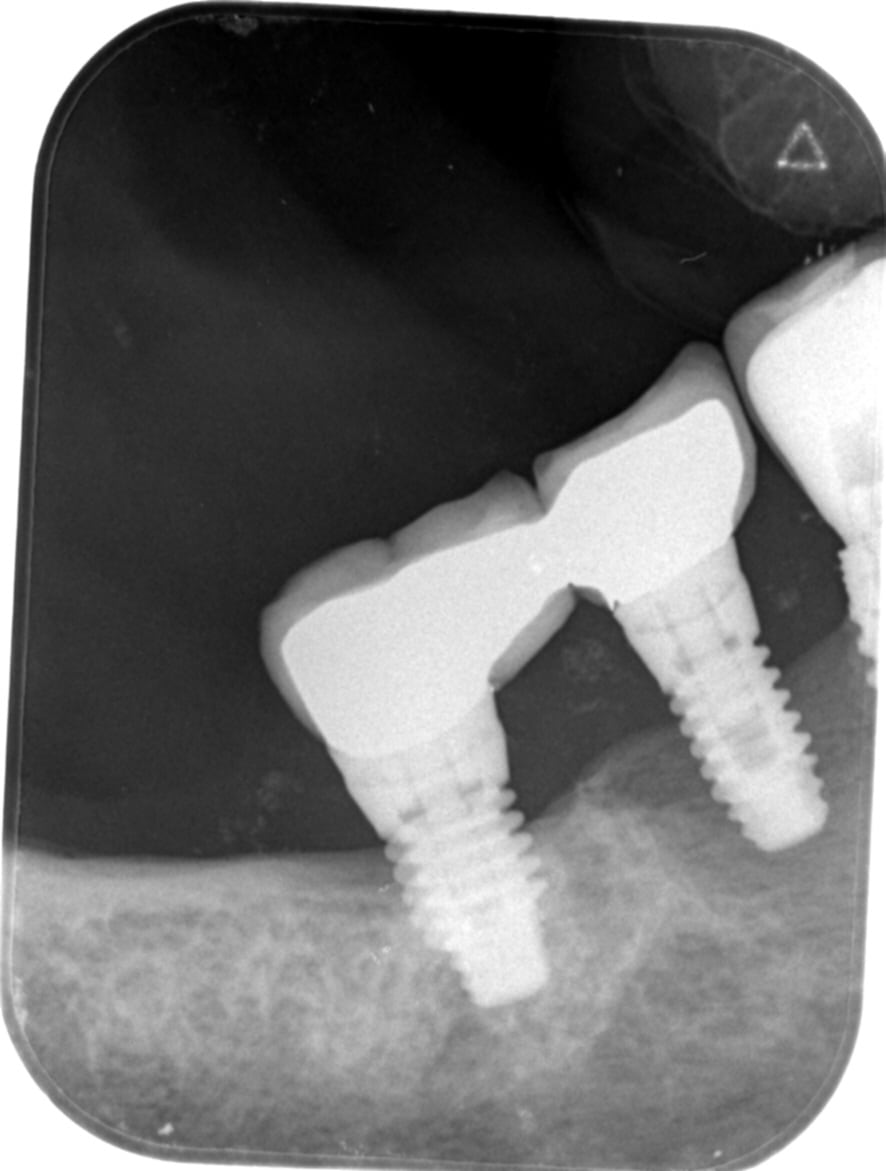

Reconnaissez vous ces implants . Le mesial a été enlevé mais je garde la distal et je dois refaire une couronne .

Et la radio n’est pas super bien orthogonale donc ça me laisse dans les 150 correspondances….

plus orthogoanle mais de l autre cote je pensais à des implants dentium